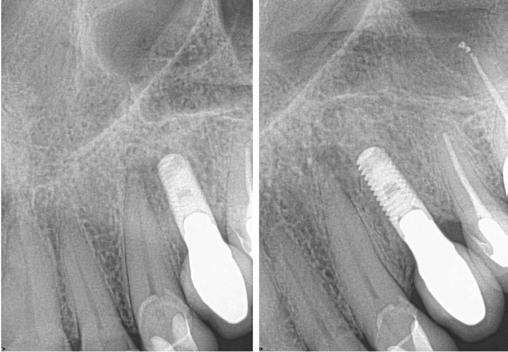

The patient was anesthetized with topical benzocaine and 3.4mL Septocaine (Articaine hydrochloride 4% and epinephrine 1:100,000) (Septodont, Saint-Maur-Fosses, France) via buccal and lingual infiltration. A rubber dam was placed, and the root canal system was accessed through the crown. Working length was obtained with Root ZX II apex locator (J. Morita, Kyoto, Japan) and verified with a periapical radiograph to be 24 mm. The tooth was then mechanically instrumented with WaveOne® rotary files (Dentsply Sirona, Charlotte, North Carolina) using 10mL of 6% NaOCl throughout the procedure. A final irrigation with EDTA (3mL) and SmartLite Pro EndoActivator™ (Dentsply Sirona, Charlotte, North Carolina) for 1 minute, followed by 6% NaOCl and activator for 1 minute was completed prior to obturation. Obturation was performed with EndoSequence® BC sealer (Brasseler

6A-6D: 6A. Preoperative periapical radiograph of

proper working

radiograph of tooth No. 11 confirmed proper master cone

periapical radiograph of tooth No. 11 verified length control and appropriate obturation

Figures

tooth No. 11. 6B. Periapical radiograph of tooth No. 11 confirmed

length. 6C. Periapical

fit. 6D. Postoperative

USA, Savannah, Georgia) and gutta percha via continuous wave condensation. EndoSequence BC liner blue (Brasseler USA, Savannah, Georgia) was placed over the gutta percha at the canal orifice, and the tooth was temporized using a cotton pellet and Fuji IX placed in the access (Figure 6). Following completion of the root canal, the patient was scheduled for a 3-month reevaluation and referred to her provider for definitive restoration. Healing was observed at the 3- and 6-month postoperative visits. Periapical radiographs were exposed at each visit revealing bony healing (Figure 7). The patient reported no pain or symptoms following nonsurgical root canal treatment. At both visits, percussion and palpation were negative. A CBCT was captured at the 6-month postoperative exam to evaluate healing. Coronal CBCT slices revealed a reduction in lesion size to 3.5 mm x 1.6 mm. Sagittal slices also showed reduction in lesion and maintained health of bone surrounding implant No. 12 (Figure 8). A 2011 article by Ng outlines eleven factors that, if present, improve periapical healing following primary non-surgical root canal treatment.17 Only two of these eleven factors, absence of a preoperative periapical lesion and size of the preoperative periapical lesion, were not met in this case report. Along with this and the 2017 AAE Treatment Options for the Compromised Tooth: A Decision Guide article, the final prognosis for healing is favorable.16

Figures 7A-7C: 7A. Immediate postoperative periapical radiograph. 7B.Periapical radiograph of tooth No. 11 at the 3-month reevaluation showing a reduction in size of the periapical radiolucency. 7C. Periapical radiograph of tooth No. 11 at the 6-month reevaluation showing a further reduction in the size of the periapical radiolucency.